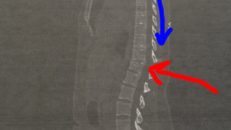

Jag ligger tryckt mot mattan och gråter och svär. Runt omkring mig hämtar Viktors familj kuddar och filtar, de håller mina händer och pratar med mig. Jag känner mest smärta och ”fan fan fan”. Försöker få in luft i lungorna mellan smärtvågorna. Efter ett tag kommer ambulanssjukvårdare som lyfter mig från mattan och in i en ambulans, jag får smärtstillande och körs till akuten. Där kommer åtta doktorer som vrider och vänder och känner på mig innan jag skickas direkt upp till magnetröntgen. Jag är fixerad vid en bår och kan inte röra mig en millimeter. Jag är törstig och snurrig och illamående av allt morfin. Efter ett tag kommer en sköterska ner och berättar att röntgenplåtarna visar en fraktur på den nedersta kotan i bröstryggen, den ska vara rund men är nu kilformad. Jag har brutit ryggen. Livrädsla, panik och gråt. Helvete också! Vad innebär det här?

Ja, vad innebär det att bryta ryggen? Jag vet inte riktigt. Men jag vet att jag har en fraktur på TH12, vilket är den sista kotan i bröstryggen. Jag vet att ryggen var såpass stabil på egen hand att det inte behövdes operation. Jag vet att jag ska gå med korsett dygnet runt i tre månader. Jag vet att mina muskler i armar, ben och kropp blir svagare för varje vilodag. Jag vet att jag inte får böja mig framåt, vrida mig eller lyfta saker. Jag vet att jag har lite svårt när jag tar på mig strumpor och skor. Jag vet att jag har lite svårt när jag torkar mig efter jag varit på toaletten. Jag vet att jag är svag i ryggen och blir trött om jag sitter eller står en längre stund. Jag vet att jag just nu inte kan göra allt jag vill göra. Men jag vet också att jag nu nästan är helt utan smärta. Jag vet att jag nu en vecka efter utskrivning från sjukhuset är ute och går promenader. Och jag vet att jag ska åka skidor i vinter. Jag vet att jag klarar av det här, vad det här än innebär.